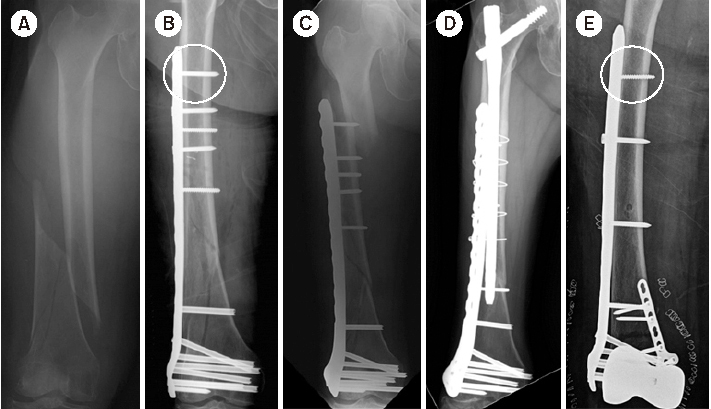

Fig. 6

(A) Radiograph of a distal femur fracture of a 74-year-old female after a ground-level fall. (B) Postoperative radiograph after a closed reduction and minimally invasive locked plating. (C) Six-week postoperative radiograph showing a stress riser fracture around the outermost locking screw after slip-down injury. (D) Radiograph showing bony union two years after overlapping intramedullary nailing. (E) Postoperative radiograph showing locked plating using a conventional cortical screw instead of a locking screw as a proximal outermost screw to minimize the stress riser.

Fig. 8

(A) Schematic diagram showing the axial shape of the distal femur and the protrusion of distal locking screw. (B) True anteroposterior radiograph showing that the lengths of the distal locking screws appear to be appropriate. (C) Radiograph taken after rotating a thigh approximately 25° internally, showing the protrusion of multiple screws across the medial cortex.